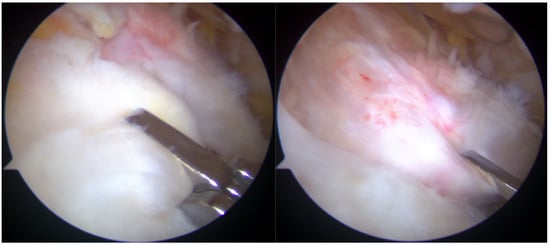

Arthroscopic visualization revealed multiple layers of the rotator cuff. Sheets 2 and 3 of the infraspinatus tendons were identifiable, while only sheet 3 of the supraspinatus tendon was visible, with sheet 2 absent (Figure 3). The mobilization of the rotator cuff confirmed that restoration to the footprint could be achieved without excessive tension (Figure 4).

Figure 3.

Subacromial view demonstrating full-thickness rotator cuff tear involving the supraspinatus (S) and infraspinatus (I) tendons. Only sheet 2 of the supraspinatus tendon is visible, while both sheets 2 and 3 of the infraspinatus tendon are present.

Figure 4.

Reduction maneuvers demonstrated the ability to reposition sheet 3 of the supraspinatus tendon (right image) and sheets 2 and 3 of the infraspinatus tendon (left image) back to their native footprint.

The lesion involved a full-thickness tear affecting both the supraspinatus and infraspinatus tendons, with separation into superficial bursal and deep articular layers. The layers exhibited differential retraction and elasticity; the superficial layers were more retracted compared to the deep layers. The complete reduction of the infraspinatus tendon was achieved, whereas only the deep layer of the supraspinatus tendon could be restored to the footprint due to the excessive retraction and stiffness of the superficial layer. Given the chronicity and severity of the tear, a complete anatomical repair was deemed unattainable. The frayed edges of the tendon were meticulously debrided to prepare for repair. Two suture anchors (Q-FIX 2.8 mm, Smith and Nephew, London, UK) were employed to secure the torn tendon back to its native humeral attachment using a single-row repair technique.

Post-repair arthroscopic visualization revealed a partial repair of the supraspinatus tendon, leaving a noticeable gap in the rotator cuff tissue (Figure 5).

Figure 5.

Rotator cuff repair has been achieved with two suture anchors, but a defect remained due to the absence of sheet 2 of the supraspinatus tendon.